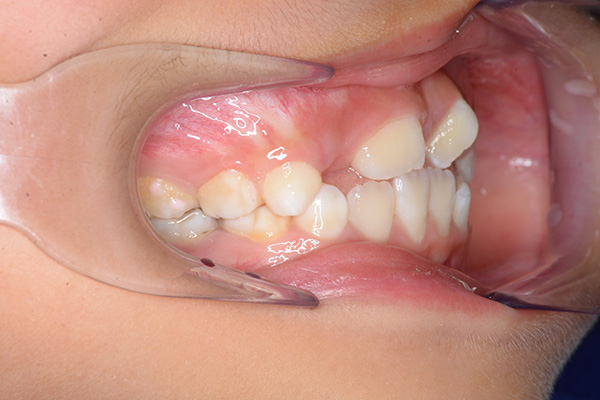

| 主訴 | 上顎前歯のでこぼこ | 診断名 | アングルⅡ級叢生症例 | ||||

|---|---|---|---|---|---|---|---|

| 初診時年齢 | 6歳9ヵ月 | 性別 | 男 | 動的治療期間 | 6ヵ月 | ||

| 既往歴として上顎正中過剰歯(2本)は抜去済み。その影響で上顎右側中切歯は捻転して萌出しており、下顎右側中切歯と早期接触が認められたため2x4(上顎のみブラケット装着)にて前歯部の改善を行った。現在は永久歯列完成まで経過観察を行い、希望があれば口元の突出感を改善するために本格矯正治療を行うことにしている。 | |

| 批評・予后 | 早期治療によって前歯部の咬合干渉は回避され、その後の永久歯への交換は順調である。 |